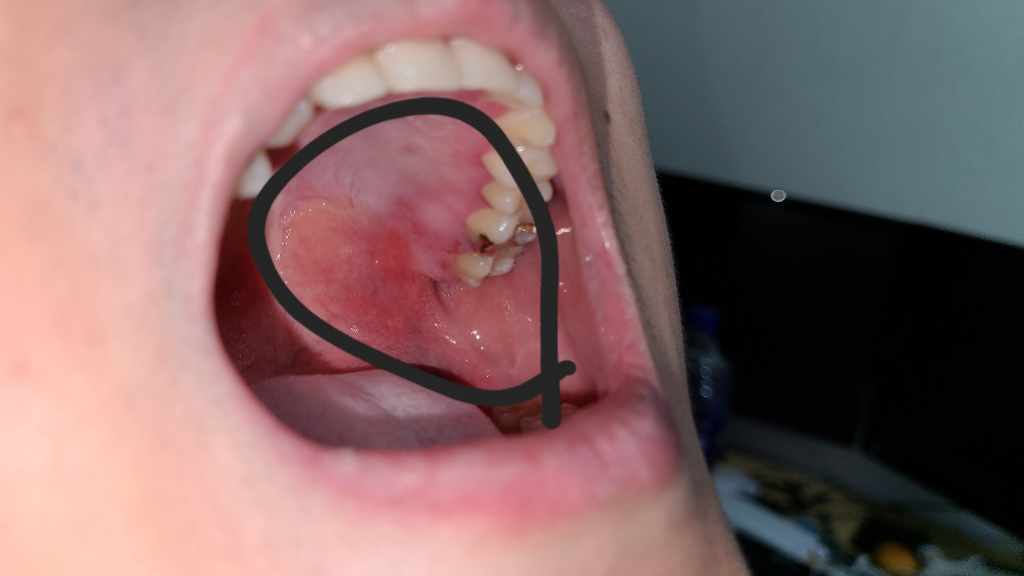

사진처럼 입안이 헐었고 성기에도 궤양이랑 뾰루지 3개정도 난 상태입니다..ㅠㅠ

• 1번 째 사진